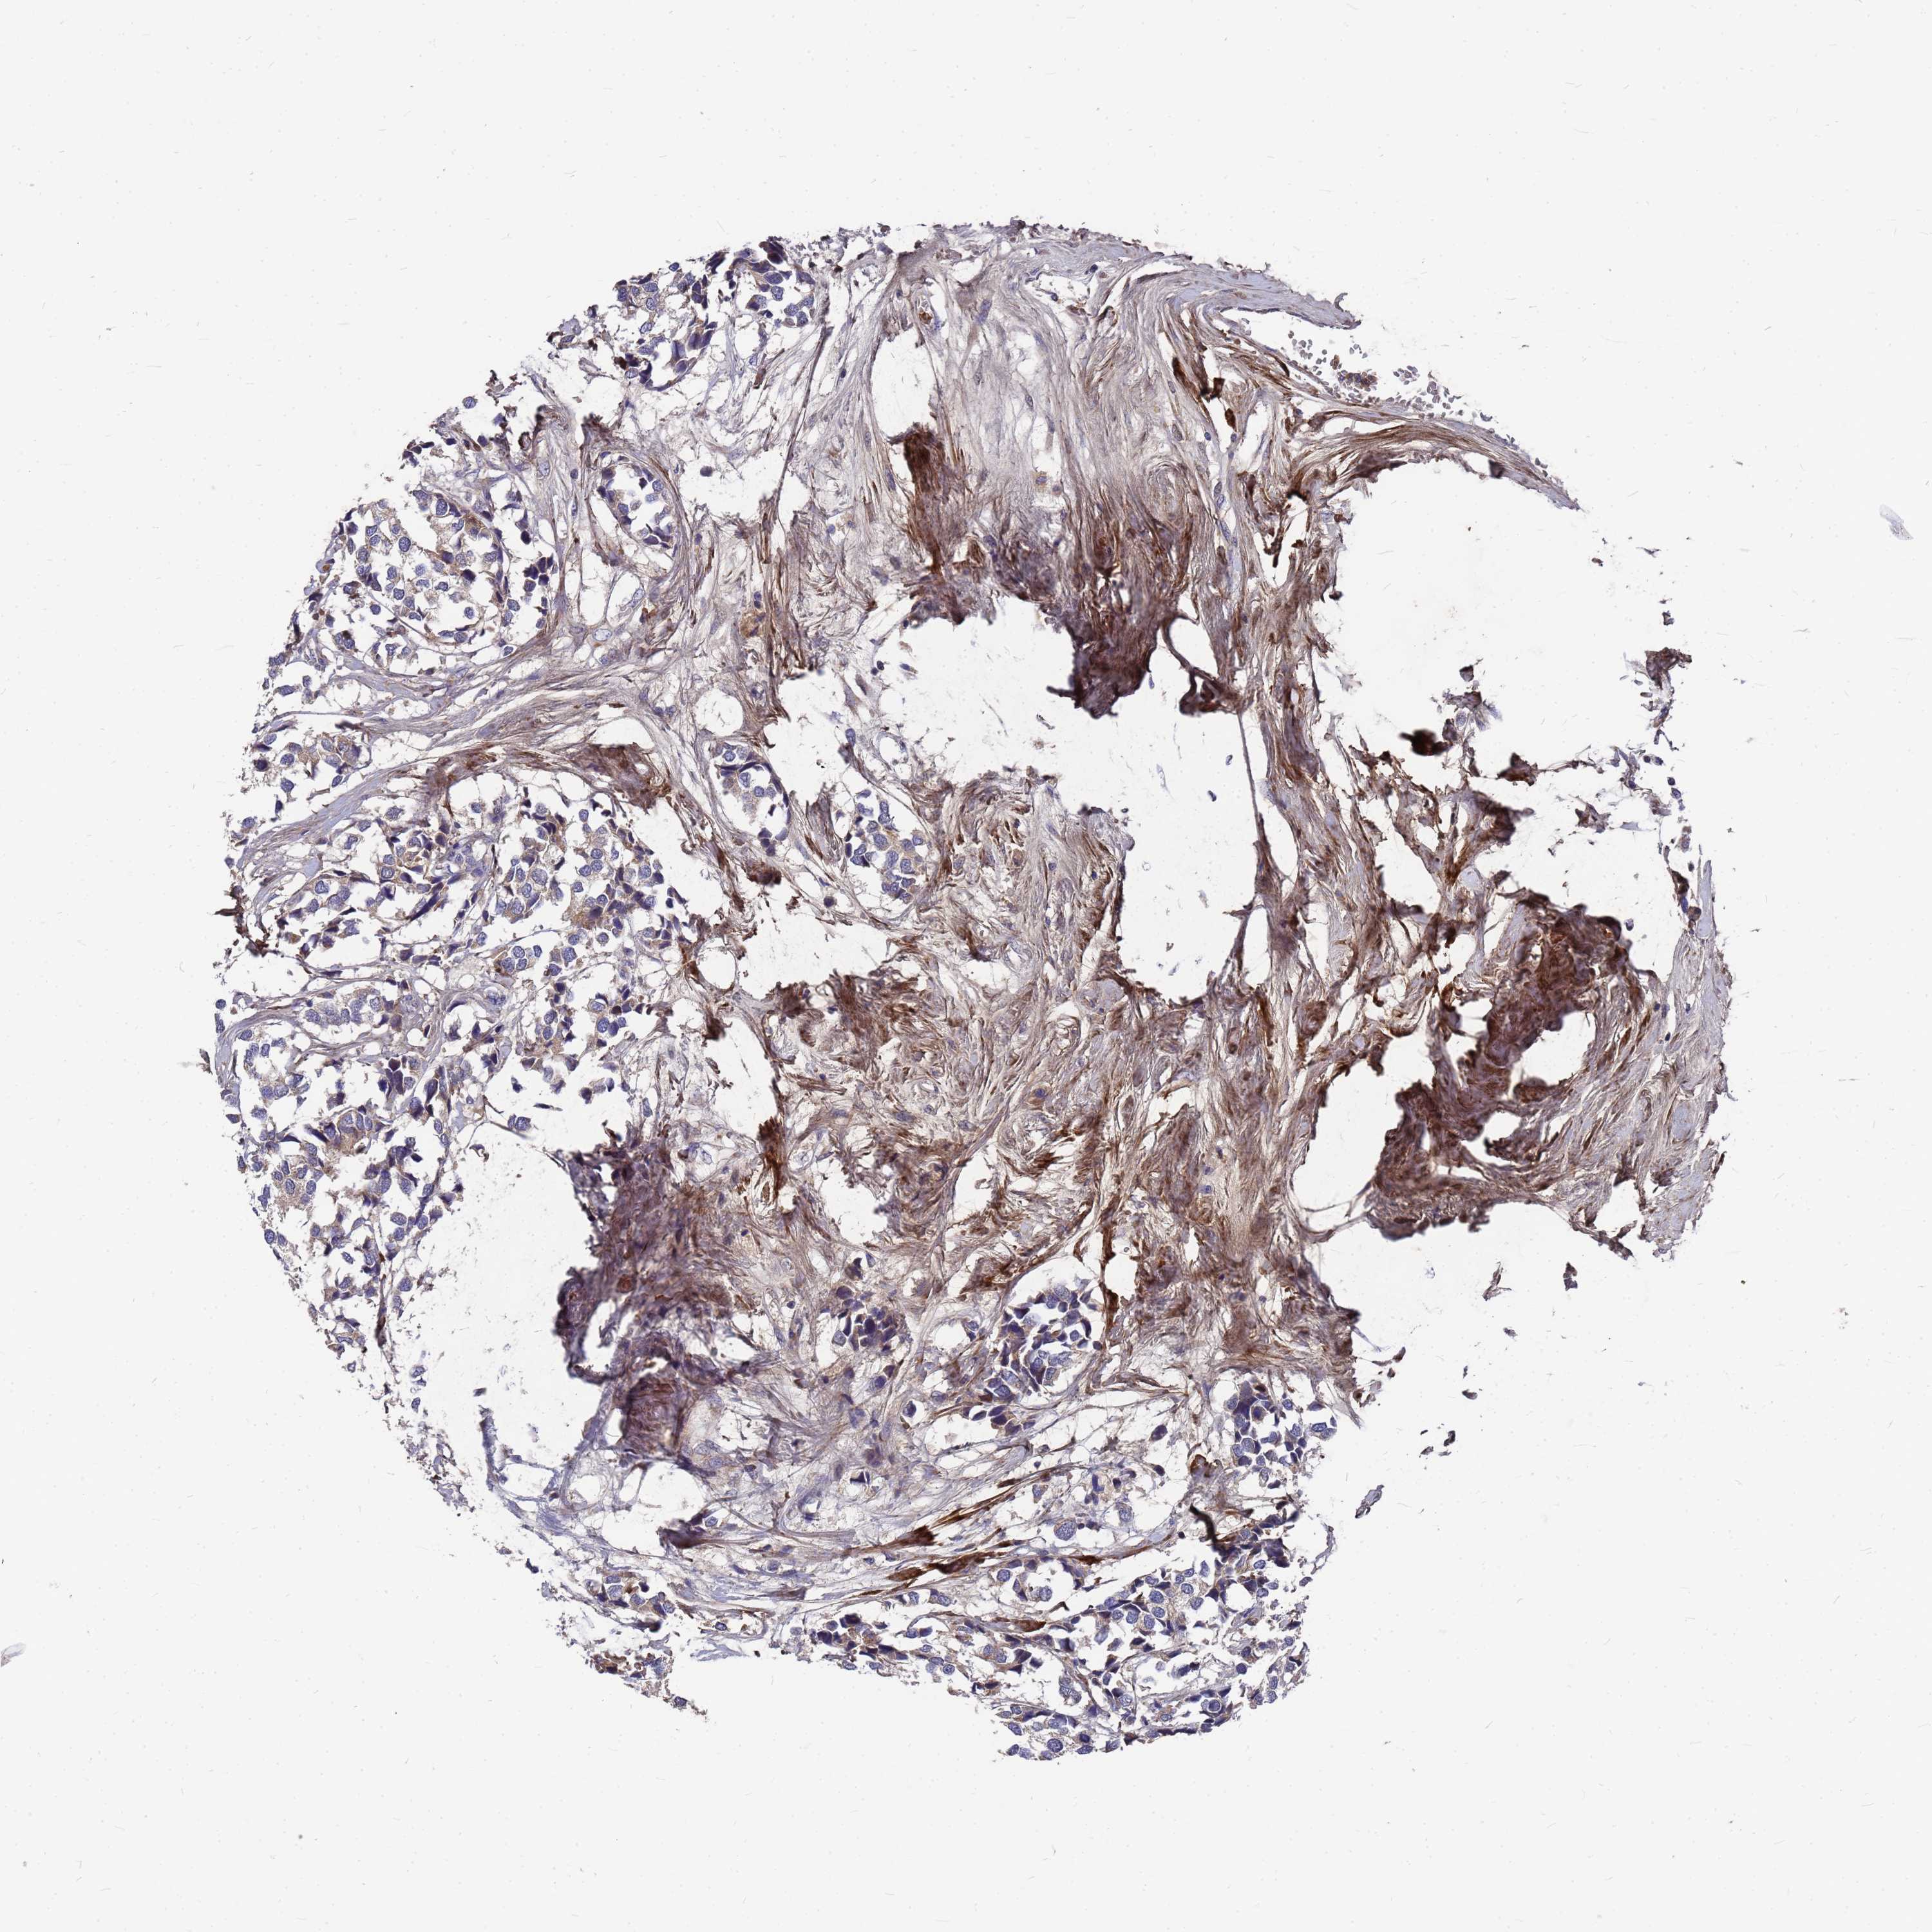

CANCER BREAST CANCER Show tissue menu

BRCA TCGA BRCA VALIDATION PROTEIN EXPRESSION